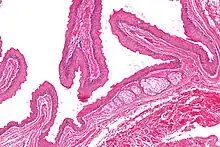

| Micrograph of a steatocystoma showing the characteristic corrugated eosinophilic lining. H&E stain | |